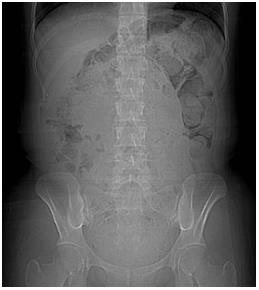

腹部X線檢查(俯臥)

體型偏瘦。大便中有空氣,可推斷糞便停滯。從盲腸到橫結(jié)腸,降結(jié)腸,乙狀結(jié)腸,直腸,以及直腸到結(jié)腸部分都有糞便停滯。診斷宿便過(guò)多。